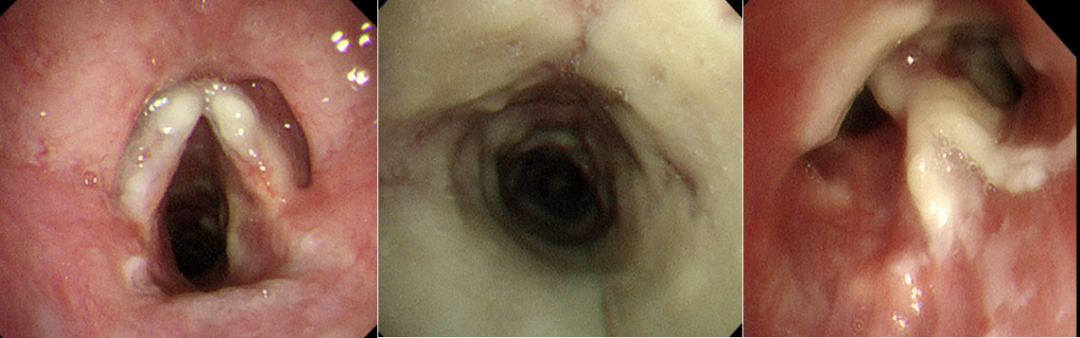

三、相似病例

病例1,男性,42岁,浙江衢州务工,油漆工,既往体健。发热半月,伴全身酸痛,咽痛,体温39℃,咳嗽,咳黄痰,当地医院拟“肺炎”住院,予抗感染治疗后无好转,转至我院,拟“社区获得性肺炎”于2023年4月7日收住。甲型流感合并气管支气管曲霉病。

图片

病例1胸部CT

病例1气管镜检查

病例2,女性,39岁,肾移植术后7个月。因“发热1周、呼吸费力伴声音嘶哑2天”于2024年1月14日入院。最终诊断为乙型流感合并气管支气管曲霉病。

病例2胸部CT

病例2气管镜检查